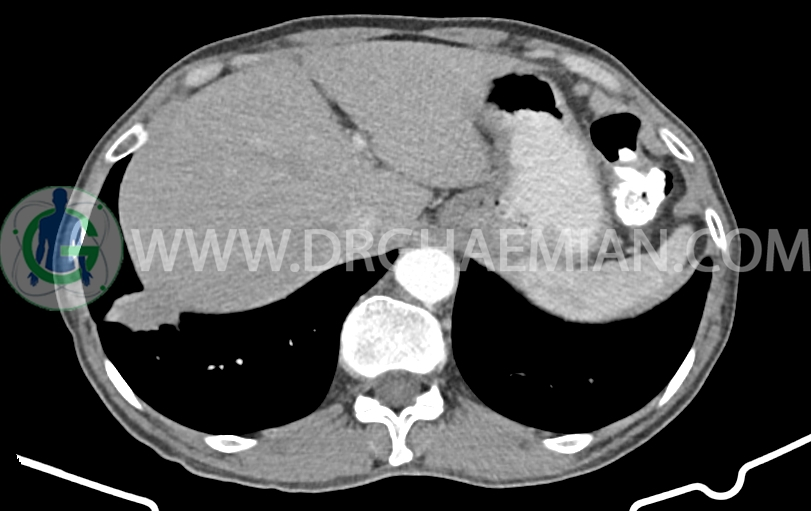

در سی تی اسکن اسپیرال ریه، مدیاستن و شکم و لگن با کنتراست خوراکی و وریدی (مولتی دیدکتور 16 با مقاطع ظریف و بازسازی های ساژیتال و کرونال) و مقایسه با سی تی اسکن 1401/06/06:

توده با حدود اسپیکوله به ابعاد mm 51x33x24 حاوی چند کانون کلسیفیه کوچک در قاعده ریه راست مجاور دیافراگم مشهود است که مطرح کننده ضایعه نئوپلازیک مثل توده اولیه و متاستاز می باشد. (نیازمند بررسی بافتی – یافته جدید نسبت به سی تی اسکن 1401/06/06 (

افزایش ضخامت ناحیه کاردیا مشاهده می شود )تطبیق با اندوسکوپی)